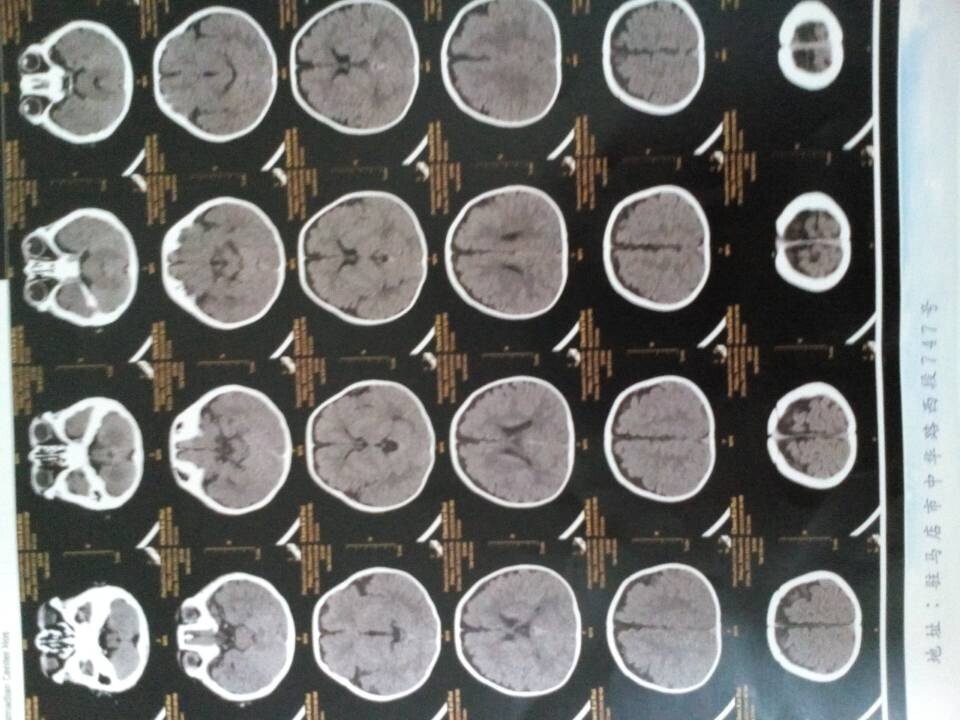

医生您好,宝宝5个月了,体检时候两腿粗细长短不一样,爱伸舌头,怎么回事,求帮助,希望给看一下 有拍ct,说是双下肢不等长 点击展开 匿名用户 2015-01-20 20:48 为您推荐: 其他回答 从ct情况看存在硬膜下腔积液情况的导致的上述情况的可能性的,这种情况需要到医院儿科看看,是不是脑损伤的情况导致的 知道张纪阳 2015-01-22 20:15 相关问题 宝宝俩月,爱伸舌头!怎么回事儿?谢谢 医生您好,我家宝宝三个半月,拉屎带有类似鼻涕似的黏液,经医院检查,是肠炎,医生给开的妈咪爱和头包地 有医生在吗?宝宝4个月了,老爱申舌头怎么回事?有宝妈知道的吗?